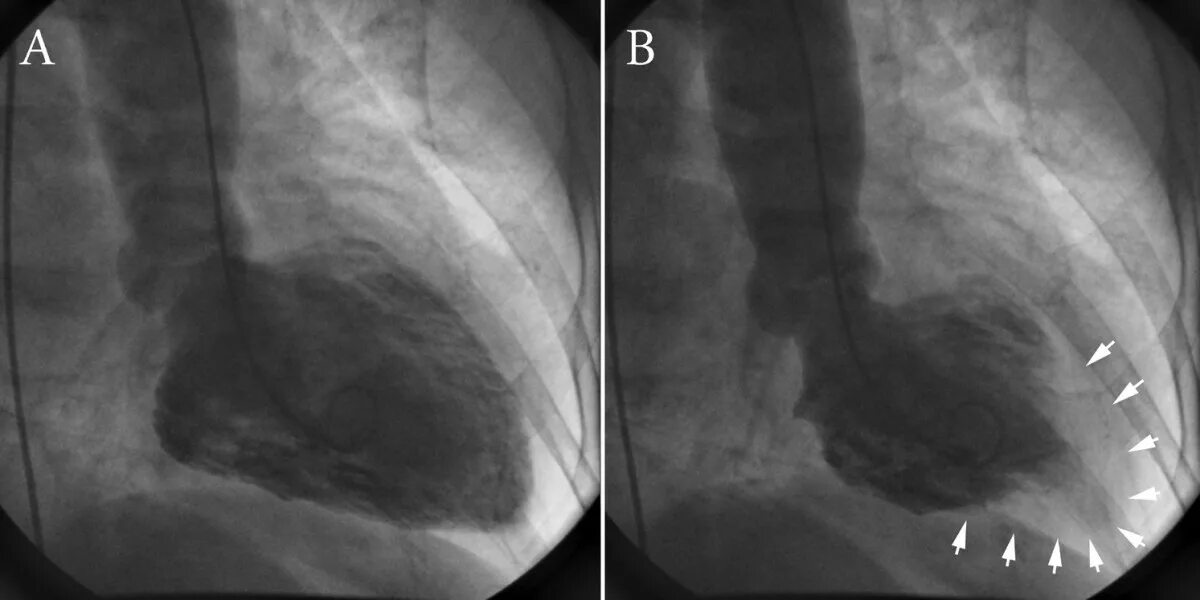

Синдром разбитого сердца симптомы